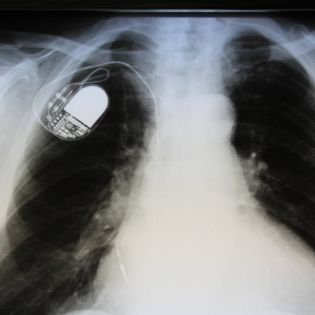

Moderne Medizin-Geräte wie Herzschrittmacher oder Insulinpumpen

sind teils nur schlecht geschützt gegen Angriffe von außen.

Fachleute sagen: Patient*innen sind darüber unzureichend

aufgeklärt. Und Herstellerfirmen reagierten auf Sicherheitslücken

oft ausweichend. Jochen Steiner im Gespräch mit Prof. Stefan

Schulz, Verhaltensmediziner Uni Trier